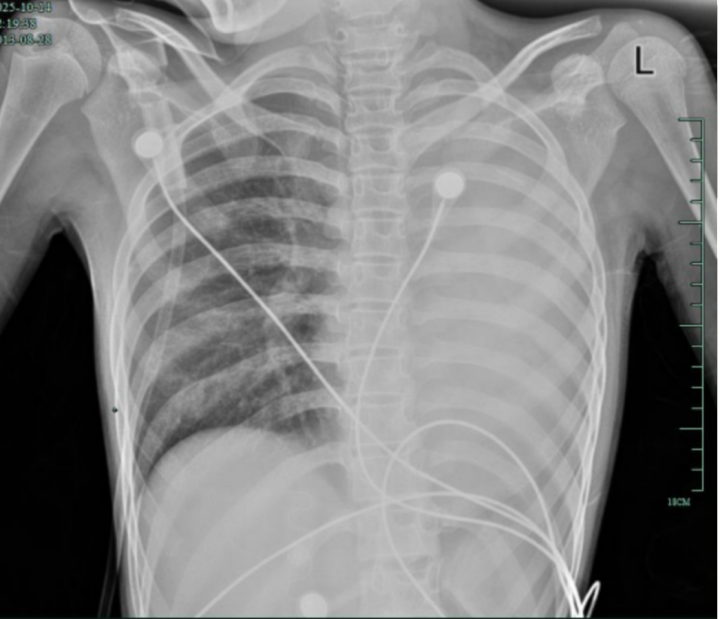

治疗前,左肺呈“白肺”状态

入院后,她很快出现呼吸急促、胸闷胸痛,只能靠 5L/min 的面罩吸氧维持血氧,胸片显示左肺已完全呈 “白肺” 改变,肺部炎症进展迅猛。

值得高兴的是,笑笑的“白肺”基本吸收,恢复如常,没有留下严重的并发症。